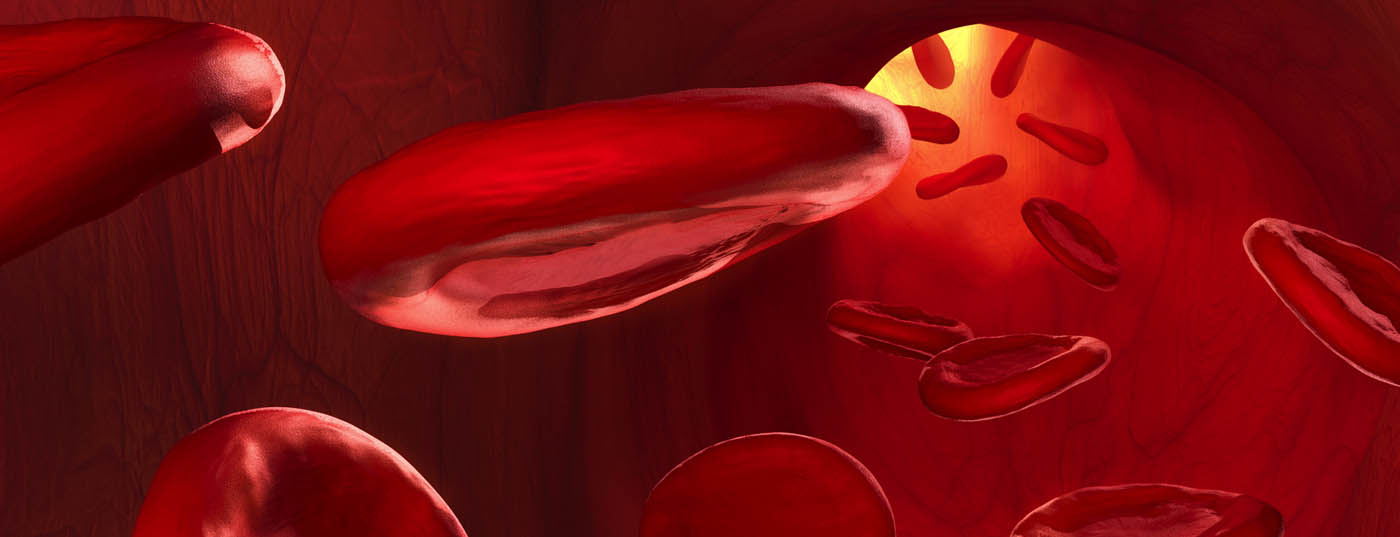

Die paroxysmale nächtliche Hämoglobinurie (PNH) reduziert die Lebenserwartung der betroffenen Patienten und schränkt ihre Lebensqualität oft drastisch ein. Eine möglichst frühe Diagnose ist äusserst wichtig, denn heute steht mit Eculizumab eine zielgerichtete Therapie zur Verfügung, welche die Prognose signifikant verbessert. Leider sind die PNH-Symptome unspezifisch. Grundversorger können dennoch viel zu einer rascheren Diagnose beitragen, indem sie an das Krankheitsbild der PNH denken.